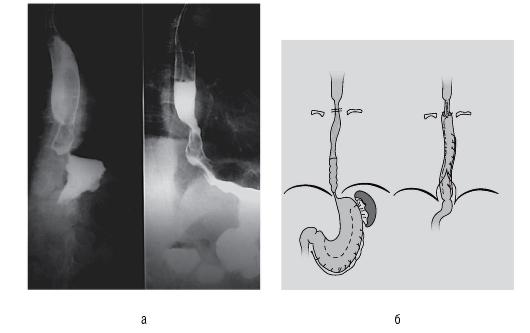

Больной, 52 лет, поступил с жалобами на дисфагию. Заболевание существует в течение нескольких лет. При рентгенологическом исследовании пищевода с бариевой взвесью в стенке пищевода выявляется ограниченный дефект наполнения с гладкими контурами и неизмененной слизистой оболочкой (рис. 30, а). Эзофагоскопия подтвердила

Рис. 29 (см. также цв. вклейку)

Рис. 30 (см. также цв. вклейку).Рентгенограмма пищевода (а) и удаленное новообразование (б) у больного, 52 лет

наличие подслизистой опухоли пищевода (рис. 30, б). Биопсия противопоказана из-за возможного повреждения слизистой оболочки, что в дальнейшем осложнит оперативное лечение и увеличит продолжительность госпитального периода.